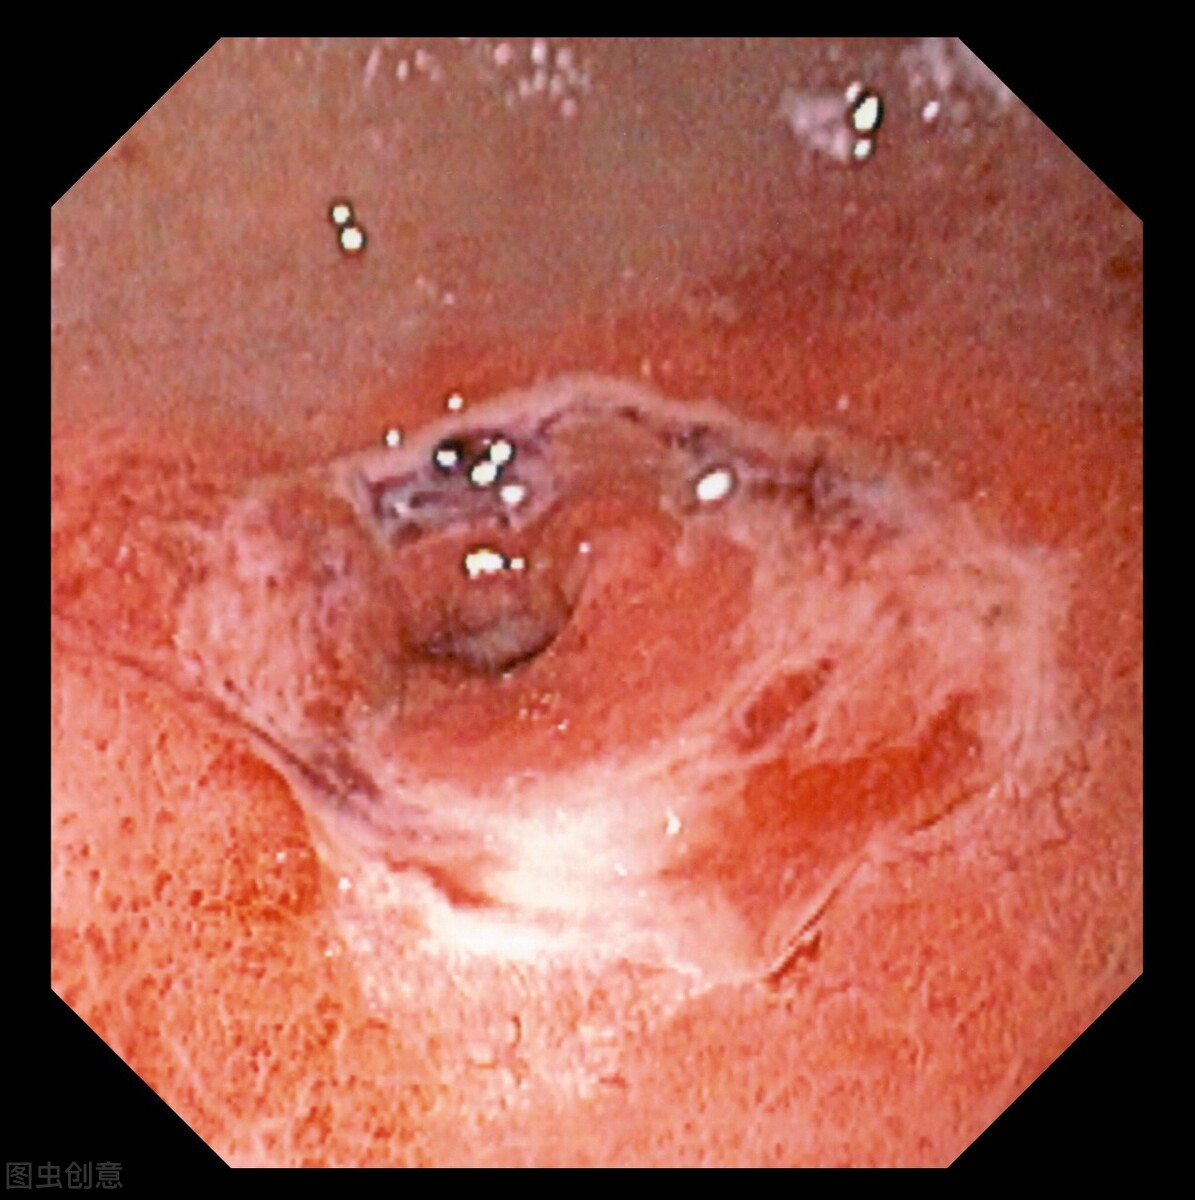

我们怎么样评估?要做什么检查? 如果是消化道出血,一般来讲现在很明确的,基本上都是需要靠内窥镜来检查,就是我们所说的下胃镜。 胃镜从口腔、食道直接看到十二指肠,甚至再向下一点,都可以看到整个胃部区域,基本上可以做到无死角地看到胃肠黏膜发生了什么变化和改变。

内窥镜除了作为检查诊断工具,现在也可以直接进行止血,它也是一种治疗措施。 如果消化道真的找不到出血的情况下,有一部分要注意到呼吸道的疾病,还有鼻咽喉的一些疾病。 但是它的临床表现是有所不同的。 像从呼吸道来的血,往往最早有呼吸道的相关症状,咳嗽、咳痰或痰中带血。 耳鼻喉科引起的出血往往有鼻黏膜干燥,或鼻黏膜常年有一些疾病,或者是有些鼻腔的症状可以判断出来。 而胃的症状,一般的出血都有明确的病史,像很多的溃疡病,有典型的慢性发病,周期性的、节律性的疼痛,这些都可以明确判断是不是有胃肠疾病。